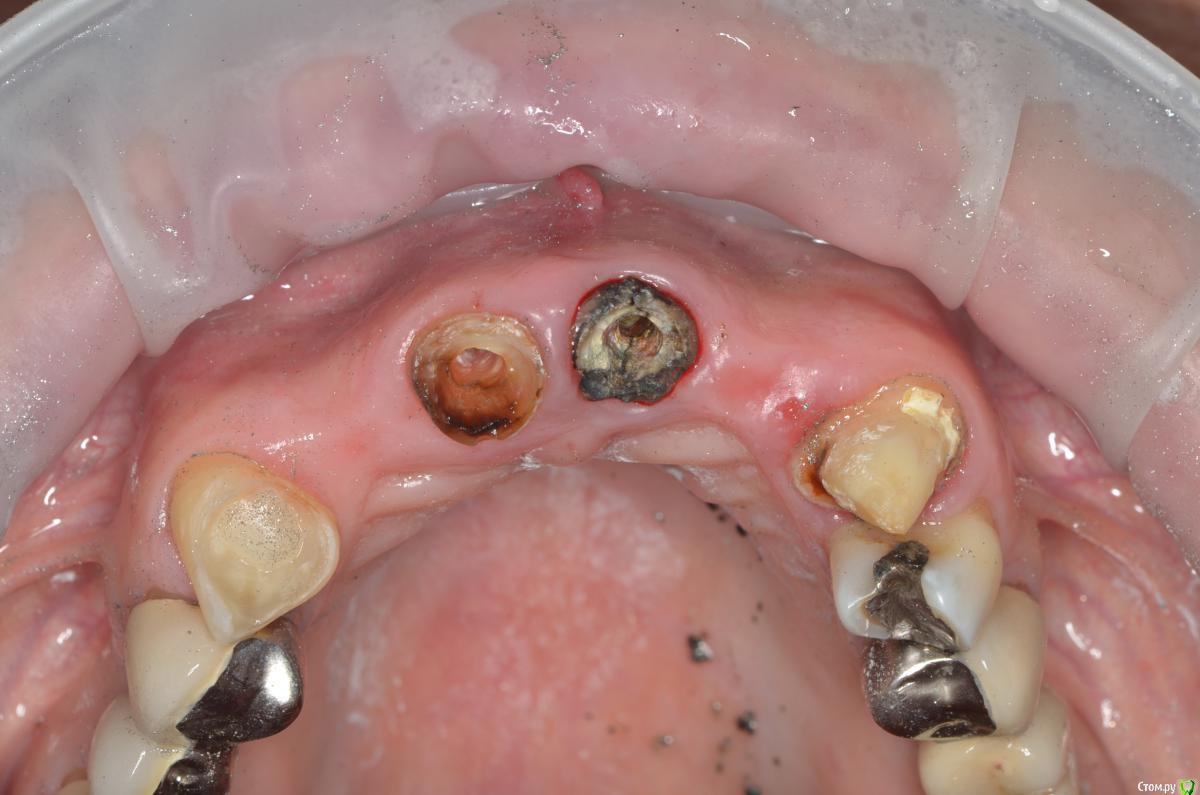

gangsta85 Опубликовано 27 сентября, 2016 Поделиться Опубликовано 27 сентября, 2016 Здравствуйте, уважаемые коллеги.Помогите пожалуйста разобраться.Центральные резцы в\ч были удалены и установлено 2 имплантата с пластикой десны, 12,22 отсутствуют в области 12 трансплантация слизистого лоскута.В тот же день изготовлены времянки по ключу с ваксапа. профиль трансгингивальной части сделан максимально под размер постоянной реставрации. 12,22 овоиды плотно прилегающие к десне.Вопросы:- Можно ли изготовить времянки сразу по форме максимально похожей на будущие реставраций и свести к минимуму коррекции профиля десны?- можно ли сделать надрез в области 22 и максимально погрузить в десну овоид 22, насколько плотно можно прижать овоид 11 в области слизистого трансплантата?- можно ли в такой ситуации добиться формирования десневых сосочков в области 12,22?-через какое время можно снять времянки для коррекции?- постоянная реставрация через 4 месяца? Что если снять слепок в день операции в лаборатории отфрезеровать времянки и установить через 1-2 дня , удастся ли в программе отмоделировать правильный профиль десны и овоиды? Как бы вы предпочли сделать времянки на CAD\CAM или в ручную? Ссылка на комментарий